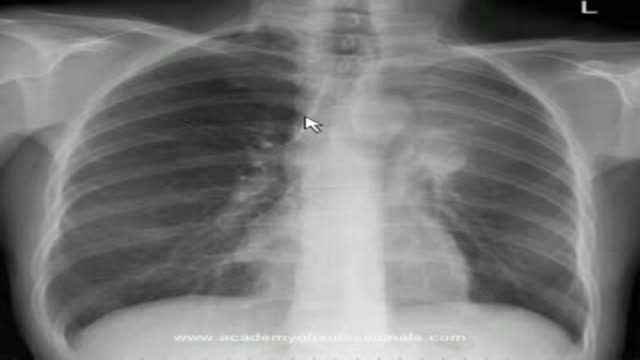

Black Salve Left an Inch Hole In Man's Hole

Watch that video of a Black Salve Left an Inch Hole In Man's Hole